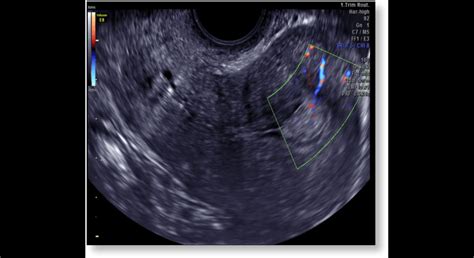

Diagnostika a liečba zväčšenej maternice